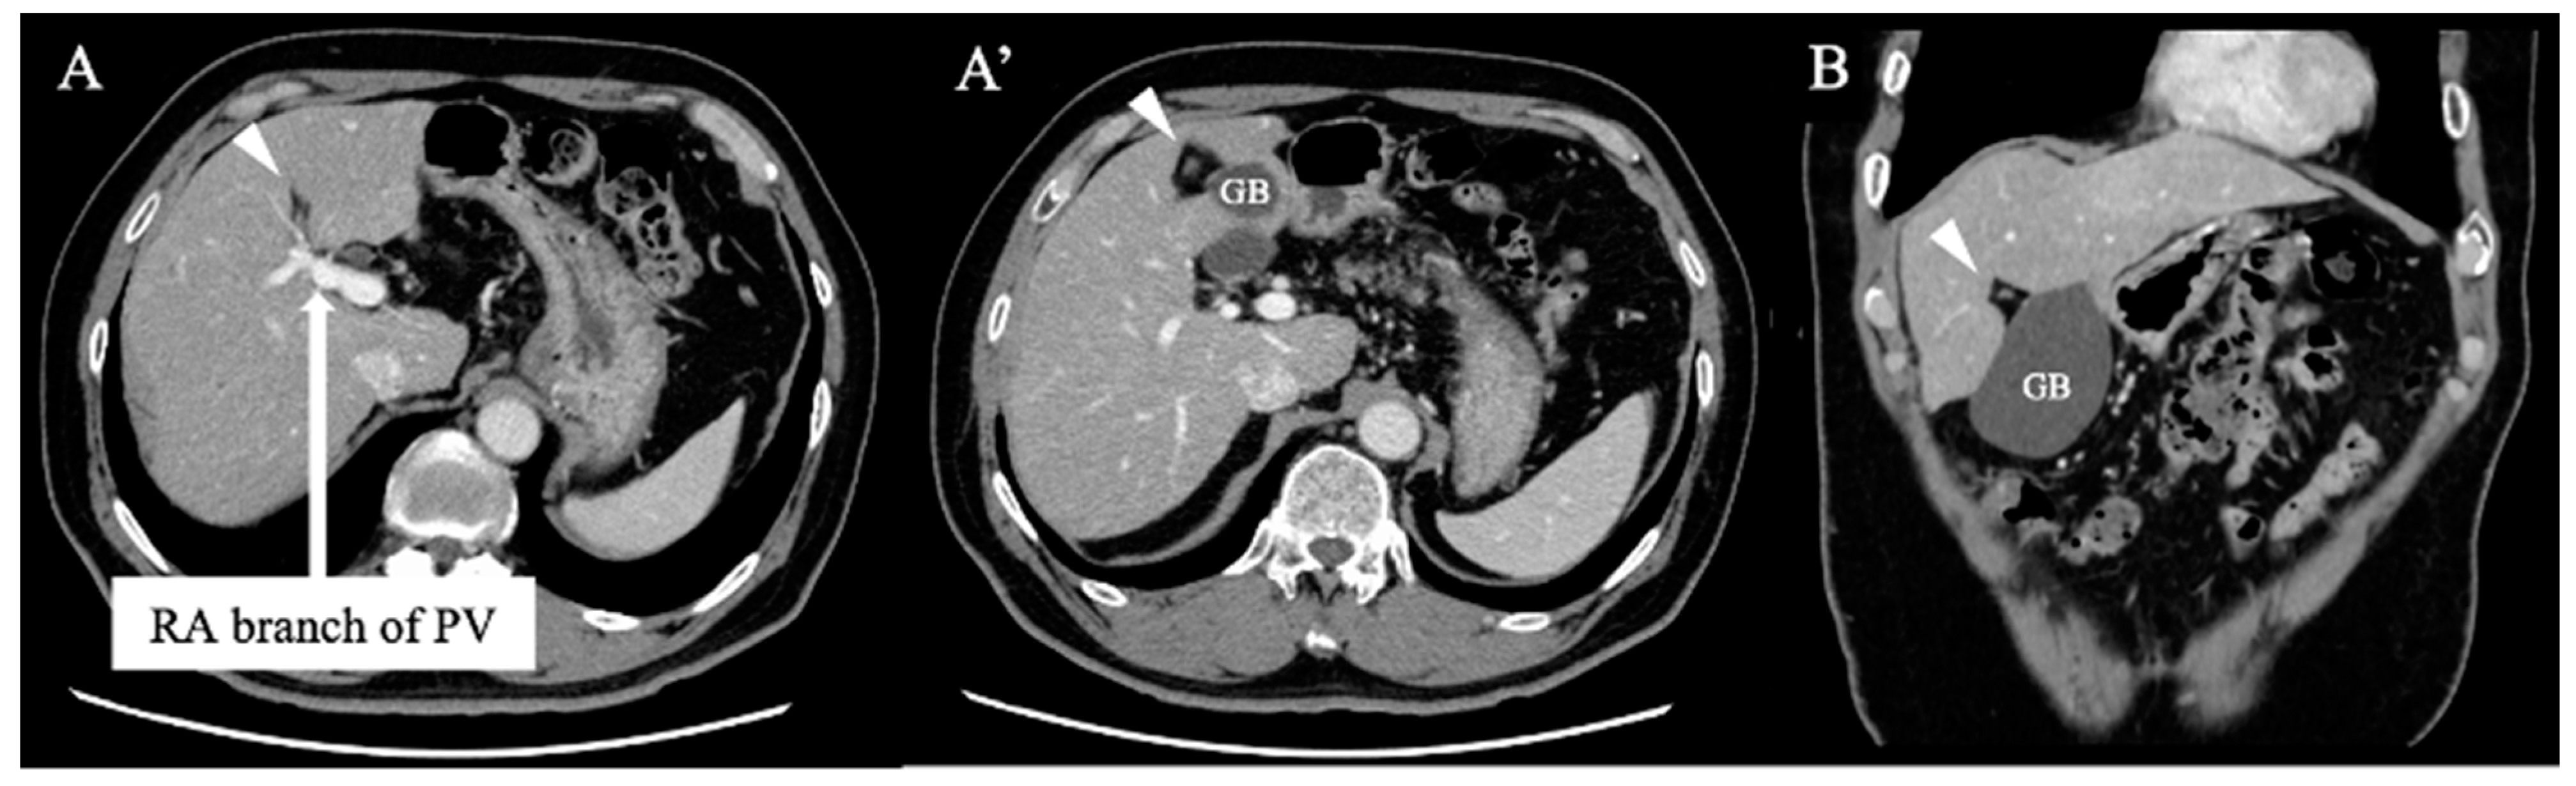

2. Case Report